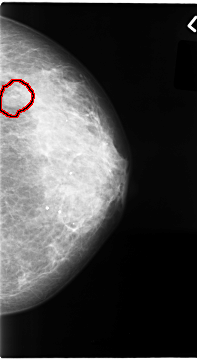

C_0065_1.LEFT_MLO

C_0065_1.LEFT_CC

FILE: C_0065_1.LEFT_CC.OVERLAY

TOTAL_ABNORMALITIES 1

ABNORMALITY 1

LESION_TYPE MASS SHAPE OVAL MARGINS MICROLOBULATED

ASSESSMENT 4

SUBTLETY 4

PATHOLOGY MALIGNANT

TOTAL_OUTLINES 1

BOUNDARY